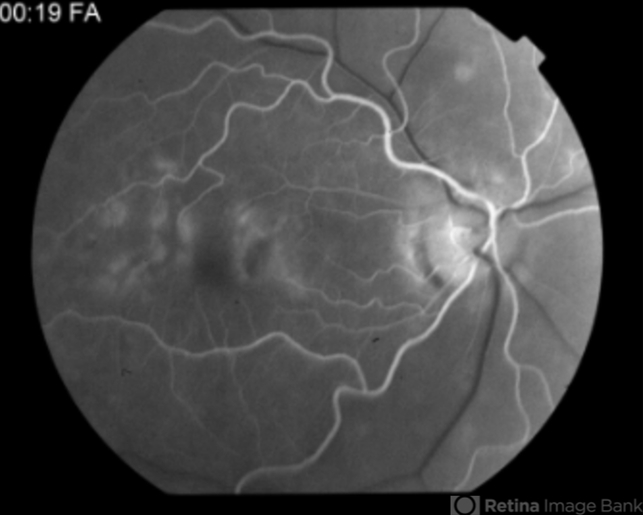

A 54-year-old woman without symptoms was referred to the retina service for assessment of maculopathy. Her visual acuities were 20/25 right and 20/20 left. She was noted to have flecks in each macula. Angiography showed a somewhat dark choroid and staining of the flecks.